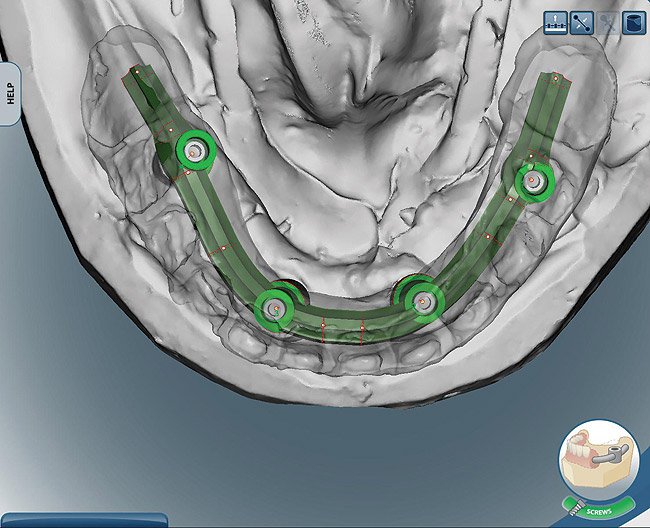

Figure 8  Upper and lower arch design of CAD/CAM titanium frames.

Figure 8

Figure 9  Upper and lower arch design of CAD/CAM titanium frames.

Figure 9

The laboratory technician made a small triad base-plate using at least two titanium provisional sleeves into the base plate. This allowed the restorative dentist to stabilize any required intermediate tooth try-ins. The teeth were set up, and a wax-up of the facial contours was produced. The facial and lingual contours of the wax-up were created as an exact replica of the finished product. The teeth were removed from the wax-up leaving a negative of the denture teeth in the wax around the arch. The master cast and baseplate without the teeth were forwarded to the bar manufacturer for scanning. Due to the fact that this particular technique and the implants can accommodate a wide range of prosthetics and abutments, high-strength zirconia or titanium substructures can be fabricated using CAD/CAM technology (Figure 8 and Figure 9).10,11 Therefore, the bar was designed on screen considering support for each tooth, and then it was milled and returned to the laboratory.